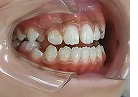

オープンバイト治療中